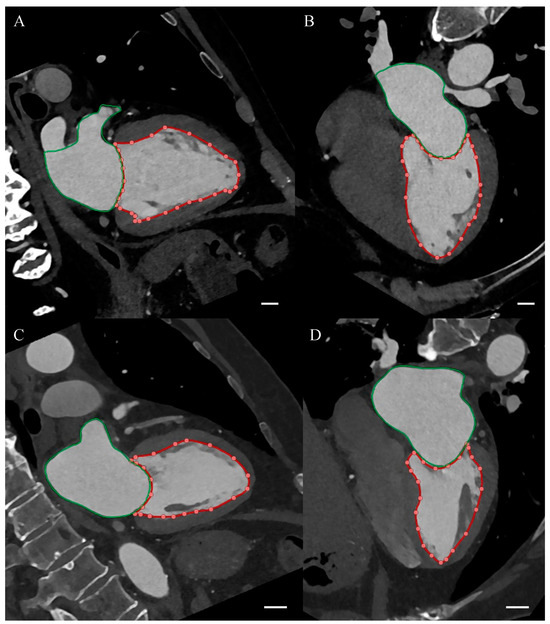

Cardiac computed tomography (CCT) was performed using the standard coronary computed tomography angiography (CCTA) protocol with dual source 384-slice CT scanner SOMATOM Force (Siemens Healthcare, Erlangen, Germany). The obtained images were assessed by a certified radiologist with EACVI Cardiac Computed Tomography Exam and over 10 years of clinical experience. The coronary artery calcium score (CACS) was assessed on native phase images of CCTA examination. The coronary artery disease severity was determined based on the Coronary Artery Disease—Reporting and Data System (CAD-RADS), where 0—documented absence of coronary artery disease (CAD), 1—minimal non-obstructive CAD (maximal stenosis: 1–24%), 2—mild non-obstructive CAD (maximal stenosis: 25–49%), 3—moderate CAD (maximal stenosis: 50–69%), 4—severe CAD (maximal stenosis: 70–99%), and 5—total coronary artery occlusion. Left atrioventricular coupling index (LACI) was calculated as the ratio of left atrial end-diastolic volume (LA EDV) to left ventricular end-diastolic volume (LV EDV), expressed as a percentage. LA EDV and LV EDV were assessed semi-automatically using the CT Cardiac Functional Analysis post-processing application (Siemens Healthcare, Erlangen, Germany). Example CCT images from a patient with LACI of 21% and 56% are presented in Figure 1.

Figure 1. Cardiac computed tomography. The red curve with dots indicates the outline of the left ventricle, the green curve indicates the outline of the left atrium. The white section in the lower right corner of each panel is 1 cm long on the image magnification scale. (A) Two-chamber view in a patient with a left atrioventricular coupling index (LACI) of 21%. (B) Four-chamber view in a patient with LACI of 21%. (C) Two-chamber view in a patient with LACI of 56%. (D) Four-chamber view in a patient with LACI of 56%.